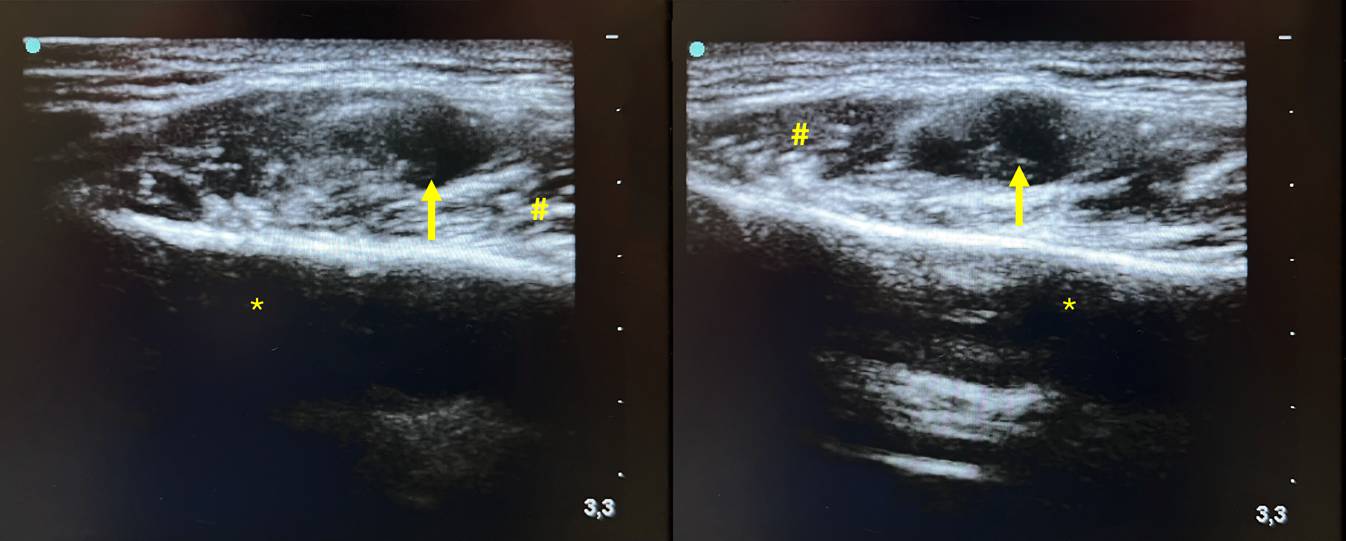

Die sonographische Kontrolle bestätigte eine 24,9 × 9,2 × 5,4 mm große, avaskuläre, inhomogene, zystische Raumforderung im linken M. masseter. Keine dorsale Schallverstärkung oder Schallschatten (Abb. 2). Zusätzlich fanden sich in den Leveln Ib und IIa links vergrößerte ovale, hilär vaskularisierte, scharf begrenzte Lymphknoten ohne Malignitätszeichen. Ein ergänzendes Orthopantomogramm (OPG) ergab keine Hinweise auf röntgendichte Fremdkörper, dentogene Foci oder anderweitige knöcherne Pathologien, die die klinischen Beschwerden erklären konnten.

Abb. 2

B‑Bild-Sonographie des Kopfes. a transversal und b longitudinal. rf Raumforderung, uk Unterkiefer, m. masseter M. masseter

Nach zunächst erfolglosem konservativen Therapieversuch wurde die Indikation zur vollständigen chirurgischen Exstirpation der Raumforderung gestellt. Der Eingriff wurde in Intubationsnarkose über einen intraoralen Zugang durchgeführt. Die Inzision erfolgte in üblicher Weise entlang der ventralen Begrenzung des Ramus mandibulae, ossär krestal vom Processus coronoideus bis zur Regio 37. Die Präparation erfolgte unter konsequenter digitaler Palpationskontrolle. Mithilfe kontinuierlicher intraoperativer Sonographie konnte die Läsion in der Tiefe des linken M. masseter lokalisiert und unter spitz-stumpfer Präparation sukzessive freigelegt werden (Abb. 3 und 4). Makroskopisch war die Raumforderung schwer von der umgebenden Muskulatur abgrenzbar. Nach vollständiger Mobilisation gelang die Entfernung der Raumforderung in toto. Sämtliche Proben wurden zur histopathologischen Aufarbeitung eingesandt (Abb. 5). Nach sorgfältiger Hämostase erfolgte ein spannungsfreier, mehrschichtiger speicheldichter Wundverschluss mit resorbierbarem Nahtmaterial. Abschließend wurde ein Kopfdruckverband angelegt.

Kontinuierliche intraoperative B‑Bild-Sonographie mit Darstellung der Raumforderung (Pfeil) von extraoral. Asterisk Corpus mandibulae, Raute M. masseter